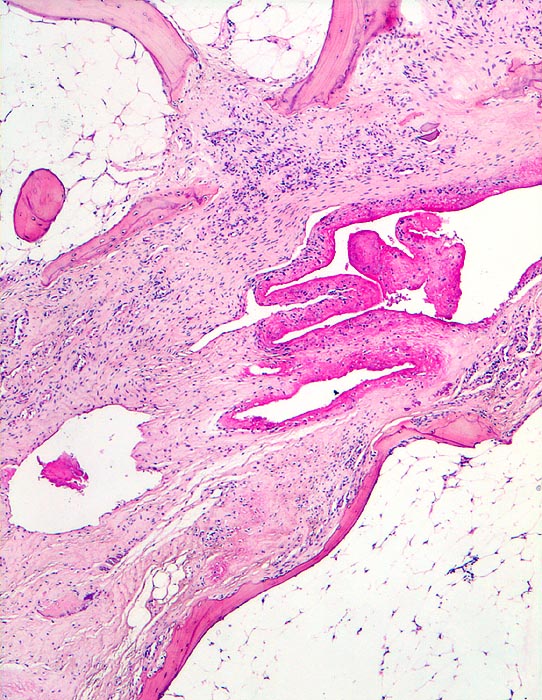

Rheumatoide Arthritis: Ankylose

Systemerkrankung/Immunpathologie

Gelenk, Hand

Knochen, Knorpel, Gelenke

Die Gelenkflächen sind durch bindegewebiges Pannusgewebe zerstört, welches den Gelenkknorpel resorbiert hat. Der Pannus überbrückt und fixiert den Gelenkspalt. Wenig Fibrinauflagerungen im Gelenkspalt.

Langjährige rheumatoide Arthritis mit Deformation der Fingergelenke und Ulnardeviation der Finger.